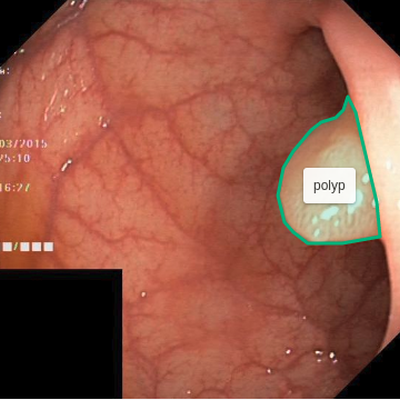

The goal of image segmentation is to assign a label to each pixel of the image so the pixels with the same label share specific characteristics, e.g., the pixels covered by the outline in the Figure 1 show a polyp. Manual segmentation by physicians is still the gold standard for most of the medical imaging modalities, for example, Magnetic Resonance Imaging for evaluating hippocampal atrophy in Alzheimer’s Disease [5] and tumor segmentation of glioma [27]. However, manual image segmentation is tedious, time-consuming, and subject to physician’s bias and inter-observer variation. Therefore, there is a need for an automated and efficient image segmentation technique.

Figure 1 shows example frames from the kvasir dataset where we have additionally marked the polyp tissue with green outline. After annotation, we exported the files to generate masks for each annotation. The exported JSON file contained all the information about the image and the coordinate points for generating the mask. To create a mask, we used ROI coordinates to draw contours on an empty black image and fill the contours with white color. The generated masks are a 1-bit color depth images with white foreground and black background. Figure 2 shows example images, their corresponding segmentation masks and bounding boxes from the Kvasir-SEG dataset.